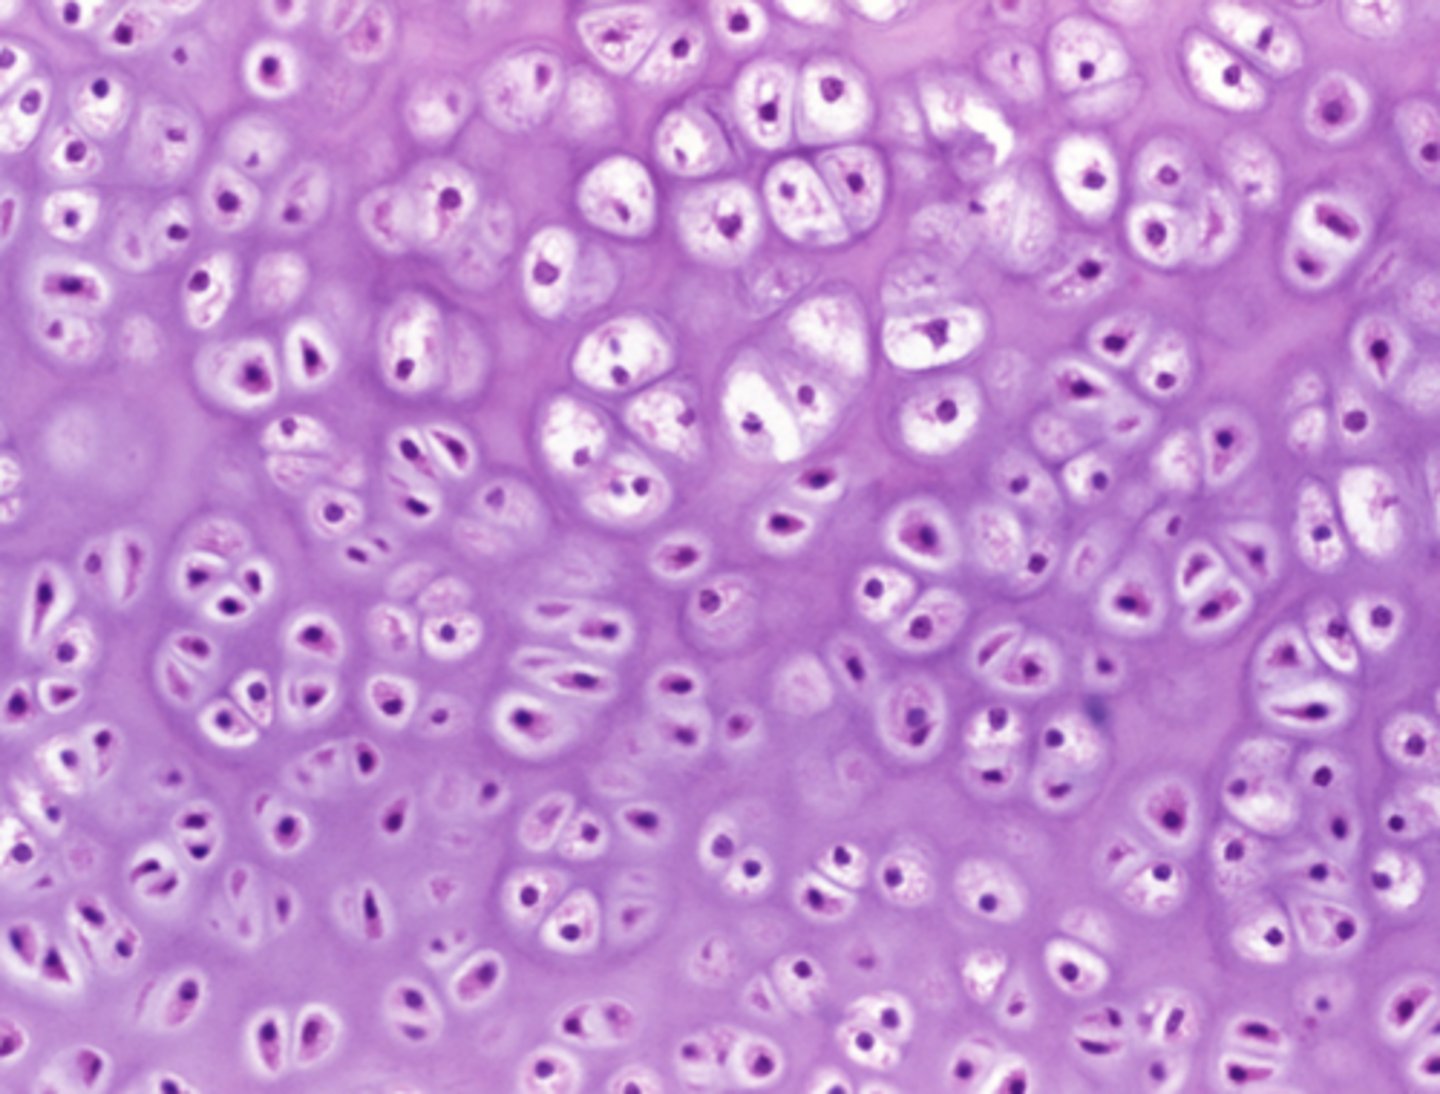

Which of the four major tissue types is presented in the following image of the distal femur:

Flexible extracellular matrix with no blood or nerve supply

Which feature in the previous image is responsible for cushioning the body from mechanical impact?

Flexible extracellular matrix with no blood or nerve supply

Basement membrane supporting the cells' basolateral surface

Rigid extracellular matrix rich in calcium

Densely packed actin and myosin filaments